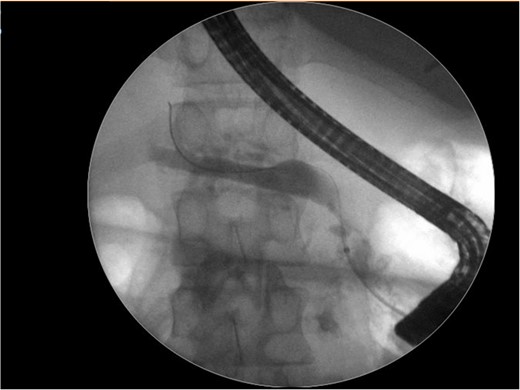

He underwent two endoscopic retrograde pancreatography. In the last- one, the pancreatic duct was cannulated, and an unsuccessful attempt to place a prosthesis due to pancreatic stenosis (Fig. 3).

Endoscopic retrograde pancreatography shows an unsuccessfully cannulated pancreatic duct.